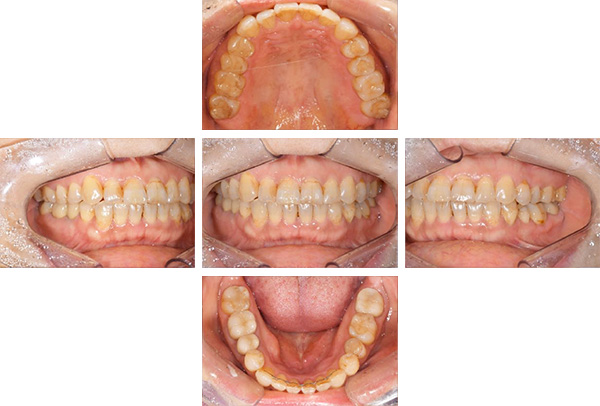

インレー症例

治療前

治療後

治療期間 4回(1ヶ月)

費用 ・セラミックインレー10本

合計:550,000円

治療リスク・副作用 ・詰め物、被せ物をする時は自分の歯を削ることになります

・歯ぎしり・食いしばりが強い方は、セラミックが割れてしまうことがあります。